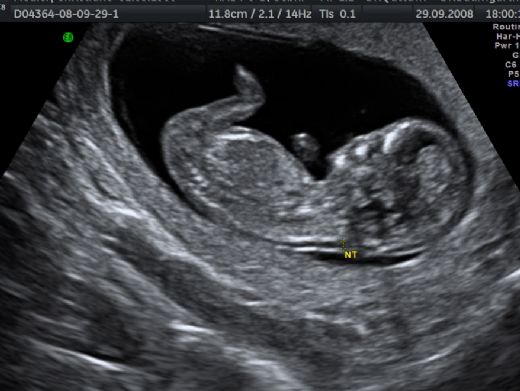

Bu belirtiler, kesin bir tanı koymak için yeterli değildir; fakat risk faktörlerinin belirlenmesi, daha ileri testler yapılmasını teşvik edebilir. Tanı YöntemleriHamilelikte Down sendromunun tanısı için çeşitli testler mevcuttur. Bu testler, genellikle ilk ve ikinci trimesterde yapılır:

Bu testlerin her biri, Down sendromu riskini değerlendirmek için kullanılabilir, ancak kesin tanı için genetik testler gereklidir. Hamilelikte Down Sendromu TedavisiDown sendromunun tedavisi, doğrudan hamilelik döneminde değil, doğumdan sonra başlar. Ancak, hamilelik öncesinde ve sırasında bazı önleyici adımlar atılabilir: